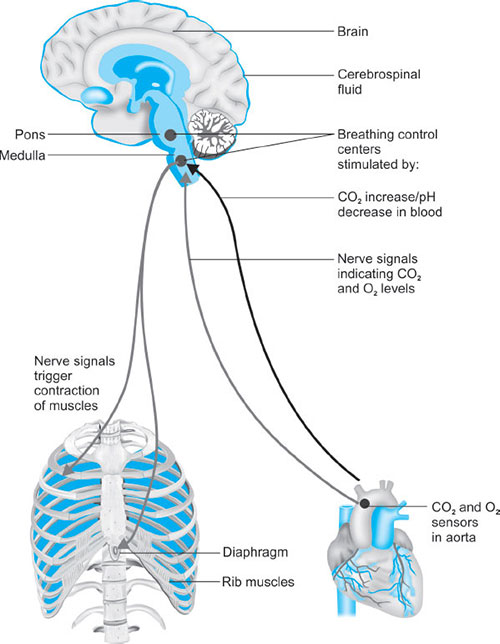

REGULATION AND CONTROL OF BREATHING (FIG. 26)

Central Control

Breathing is mainly controled at the level of brainstem. The normal automatic and periodic nature of breathing is triggered and controled by the respiratory centers located in the pons and medulla.

Medullary Respiratory Center

- Dorsal medullary respiratory neurones: Associated with inspiration. It has been proposed that spontaneous intrinsic periodic firing of these neurones responsible for the basic rhythm of breathing.32As a result, these neurones exhibit a cycle of activity that arises spontaneously every few seconds and establish the basic rhythm of the respiration. When the neurones are active their action potentials travel through reticulospinal tract in the spinal cord and phrenic and intercostal nerves and finally stimulate the respiratory muscles.

- Ventral medullary respiratory neurones: Associated with control of breathing. These neurones are silent during quite breathing because expiration is a passive event following an active inspiration. However, they are activated during forced expiration when the rate and the depth 33of the respiration is increased (e.g. exercise). During heavy breathing increased activity of the inspiratory center neurones activates the expiratory system. In turn, the increased activity of the expiratory system inhibits the inspiratory center and stimulates muscles of expiration.

The dorsal and ventral groups are bilaterally paired and there is 8 cross communication between them. As a consequence they behave in synchrony and the respiratory movements are symmetric.

Apneustic Center

It is located in the lower pons.

Exact role is not known. Lesions covering this area in the pons cause a pathologic respiratory rhythm with increased apnea frequency. What is known is nerve impulses from the apneustic center stimulate the inspiratory center and without constant influence of this center respiration becomes shallow and irregular.

Pneumotaxic Center

It is located in the upper pons.

These neurones have an inhibitory effect on the both inspiratory and apneustic centers. It is probably responsible for the termination of inspiration by inhibiting the activity of the dorsal medullar neurones. It primarily regulates the volume and secondarily the rate of the respiration. In the lesions of this area normal respiration is protected, thus it is believed that upper pons is responsible for the fine-tuning of the respiratory rhythm. Hypoactivation of this center causes prolonged deep inspirations and brief, limited expirations by allowing the inspiration center remain active longer than normal. Hyperactivation of this center on the other hand results in shallow inspirations.

The apneustic and pneumotaxic centers function in coordination in order to provide a rhythmic respiratory cycle: Activation of the inspiratory center stimulates the muscles of inspiration and also the pneumotaxic center. Then the pneumotaxic center inhibits both the apneustic and the inspiratory centers resulting in initiation of expiration. Spontaneous activity of the neurones in the inspiratory center starts another similar cycle again. Breathing in some extent is also controled consciously from higher brain centers (e.g. cerebral cortex). This control is required when we talk, cough and vomit. It is also possible voluntarily change the rate of the breathing. Hyperventilation can decrease blood partial carbon dioxide pressure (PCO2) due to loss of CO2 resulting in peripheral vasodilatation and decrease in blood pressure. One can also stop breathing voluntarily. That results in an 34increase in arterial partial oxygen pressure (PO2), which produces an urge to breathe. When eventually PCO2 reaches the high enough level it overrides the conscious influences from the cortex and stimulates the inspiratory system. If one holds his breath long enough to decrease PO2 to a very low level one may loose his consciousness. In an unconscious person, automatic control of the respiration takes over and the normal breathing resumes. Other parts of the brain (limbic system, hypothalamus) can also alter the breathing pattern, e.g. affective states, strong emotions, such as rage and fear. In addition, stimulation of touch, thermal and pain receptors can also stimulate the respiratory system.

SENSORS/OTHER RECEPTORS (FIG. 27)

Chemoreceptors

The respiratory system maintains concentrations of O2, CO2 and the pH of the body fluids within a normal range. Any deviation from these values has a marked influence on the respiration. Chemoreceptors are specialized neurones activated by changes in O2 or CO2 levels in the blood and the brain tissue, respectively. They are involved in the regulation of respiration according to the changes in PO2 and pH. O2-sensitive chemoreceptors (Peripheral chemoreceptors) are located at the bifurcation of the carotid artery in the neck and the aortic arch. They are small vascular sensory organs encapsulated with the connective tissue. They are connected to the respiratory center in the medulla by glossopharyngeal nerve (carotid body chemoreceptors) and the vagus nerve (aortic body). Central chemoreceptors are located bilaterally in the chemosensitive area of the medulla oblongata and exposed to the cerebrospinal fluid (CSF), local blood flow and local metabolism. They actually respond to changes in H+ concentration in these compartments. When the blood partial PCO2 is increased CO2 diffuses into the CSF from cerebral vessels and liberates H+. (When CO2 combines with water forms carbonic acid and liberates H+ and HCO3−).